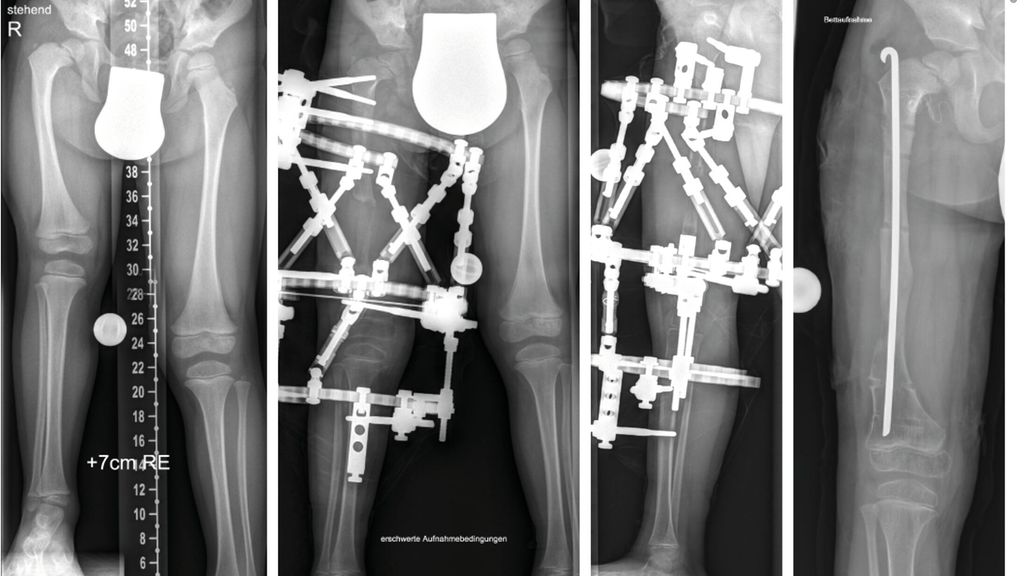

Pathologie am Kniegelenk

Sowohl beim CFD wie auch bei der FH zeigen sich deutliche Pathologien am Kniegelenk. Es besteht eine Hypoplasie der lateralen Epiphyse mit entsprechenden Wachstumsstörungen, was zu einem rezidivierenden Valgus am Kniegelenk führt.3,4 Zusätzlich besteht in vielen Fällen eine deutliche Instabilität des Kniegelenkes. Es findet sich eine Hypoplasie des ACL in etwa 15% und ein vollständiges Fehlen des ACL in etwa 85% der Fälle.5 Das PCL ist in etwa 21% hypoplastisch und in etwa 24% ebenso fehlend. Diese Instabilität des Kniegelenkes ist bei milden Formen oft klinisch im Alltag nicht relevant, kann jedoch während einer Verlängerung zu massiven Problemen im Sinne von Luxation und Subluxation führen. Zusätzlich zeigt sich oft eine Lateralisation der Patella, wobei diese auch permanent luxiert lateral am Femurkondyl liegen kann.

Die Valgusstellung kann sehr einfach über eine Wachstumslenkung (Hemiepiphysiodese mit 2-Loch-Platte) korrigiert werden. Um eine Subluxation am Kniegelenk zu verhindern, muss bei allen diesen Fällen bei Verlängerung mit Fixateur dieser knieüberbrückend montiert werden (Abb.4). Bei Verlängerung über einen Verlängerungsmarknagel wird in diesen Fällen eine Oberunterschenkelschiene (KAFO) verwendet und prophylaktisch, soweit noch vorhanden, die Fascia lata auf Höhe des oberen Patellapols durchtrennt. Bei deutlicher Instabilität oder auch Subluxation ist eine Stabilisierung über eine komplexe Operation, die als Super-Knee-Operation subsumiert wird, erforderlich.2 Diese Operation kann auch an die Hüftrekonstruktion/Super-Hip-Operation angeschlossen werden, da hier die Faszie ohnehin präpariert wird. Je nach Alter des Patienten und dem Ausmaß der Instabilität wird hierbei die Fascia lata nach Präparation bis an das Tuberculum Gerdyi und Halbieren der Länge nach entweder extraartikulär oder intraartikulär geführt. Auch die Fixation wird abhängig vom Alter mit Biotenodeseschrauben oder Weichteilzügelung durchgeführt.

Abb. 4: Platzierung (a–d) eines Fixateur externe mit Knie-Überbau (e–g) zum Schutz vor (Sub-)Luxation